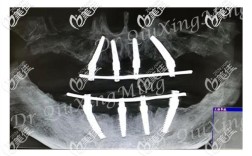

种植牙能否戴牙冠,首要前提是种植体与牙槽骨完成“骨结合”,骨结合是指种植体表面与周围骨组织之间形成直接的 structural connection,两者紧密结合,如同天然牙根与牙槽骨的关系,这一过程是种植牙稳定性和长期使用的基础,若骨结合未充分形成就过早戴牙冠,可能导致种植体松动、脱落甚至失败。

骨结合的时间受多种因素影响,通常需要3-6个月,但部分患者可能需要更长时间,骨结合的速度与牙槽骨的质量、患者的身体状况、种植体的设计等密切相关,牙槽骨条件好、骨质致密的患者,骨结合可能更快;而牙槽骨萎缩、需要进行植骨手术的患者,则需要额外等待植骨区域愈合,骨结合时间会相应延长。

- 定期复查:按医生要求复查(通常术后1周、1个月、3个月),通过X线片检查骨结合情况,及时调整治疗方案。